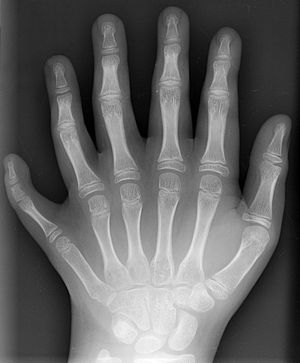

다지증은 손가락이나 발가락이 정상 개수보다 많은 선천성 기형으로, 유전자 돌연변이, 시스 조절 요소 돌연변이 등 다양한 유전적 요인에 의해 발생한다. 다지증은 발생 위치에 따라 척골성, 요골성, 중심성으로 분류되며, 다른 기형 동반 여부에 따라 단독형과 증후군형으로 나뉜다. 가장 흔한 증상은 추가 손가락이나 발가락이 나타나는 것이며, 수술적 치료는 기능적, 미용적 문제 발생 시 고려된다. 다지증은 고대부터 기록되었으며, 역사적 인물이나 문학 작품에서 묘사되기도 한다.

| 설명 | 손이나 발에 정상보다 많은 수의 손가락이나 발가락이 있는 선천적 기형이다. |

3. 분류

과잉된 손가락(발가락)은 흔적, 가는 줄기로 연결된 부유형, 완전한 형태 등 다양하게 나타난다. 인종적으로는 흑인에게서 많이 발생하지만 모든 인종에서 나타나며, 일본인의 경우 손에서는 엄지손가락, 발에서는 다섯 번째 발가락에 주로 발생한다. 브라질에서는 가족 구성원 14명 모두가 다지증인 사례도 있다.[87]

다지증은 발생 위치에 따라 척골(후축성) 다지증, 요골(전축성) 다지증, 중심성 다지증의 세 가지 주요 유형으로 나눌 수 있다.[6][8]

다지증의 가장 흔한 증상은 손가락이나 발가락 수가 정상보다 많은 것이다. 추가 손가락/발가락은 크기, 모양, 기능 면에서 다양하게 나타날 수 있다. 어떤 경우에는 추가 손가락/발가락이 피부 돌기 형태로만 존재하기도 한다. 기능적인 문제가 없는 경우도 있지만, 손이나 발의 기능 저하, 통증, 운동 범위 제한 등이 발생할 수도 있다. 드물게, 추가 손가락이 완전히 기능적인 경우도 보고되었다.[6] 덧붙은 손가락이나 발가락은 대개 제거할 수 있는 부드러운 조직의 작은 조각이다. 드물게 관절이 없는 뼈를 포함하기도 하며, 매우 드물게는 완전하고 기능적인 손가락일 수도 있다. 덧붙은 손가락이나 발가락은 손의 척골(새끼손가락) 쪽에 가장 흔하며, 요골(엄지손가락) 쪽에는 덜 흔하고, 가운데 세 손가락 안에서는 매우 드물게 나타난다.[7]

다지증은 육안으로 확인할 수 있으며, X선 촬영을 통해 뼈 구조를 자세히 확인한다.[16] 1961년, 프란츠(Frantz)와 오라힐리(O’Rahilly)는 임상 증상을 유발하는 배아의 결함을 기반으로 사지의 선천적 기형을 7가지 범주로 분류하였고, 1976년 스완슨(Swanson)에 의해 수정되었다.[35][36] 다지증은 이 분류에서 중복 범주에 속한다.[37]